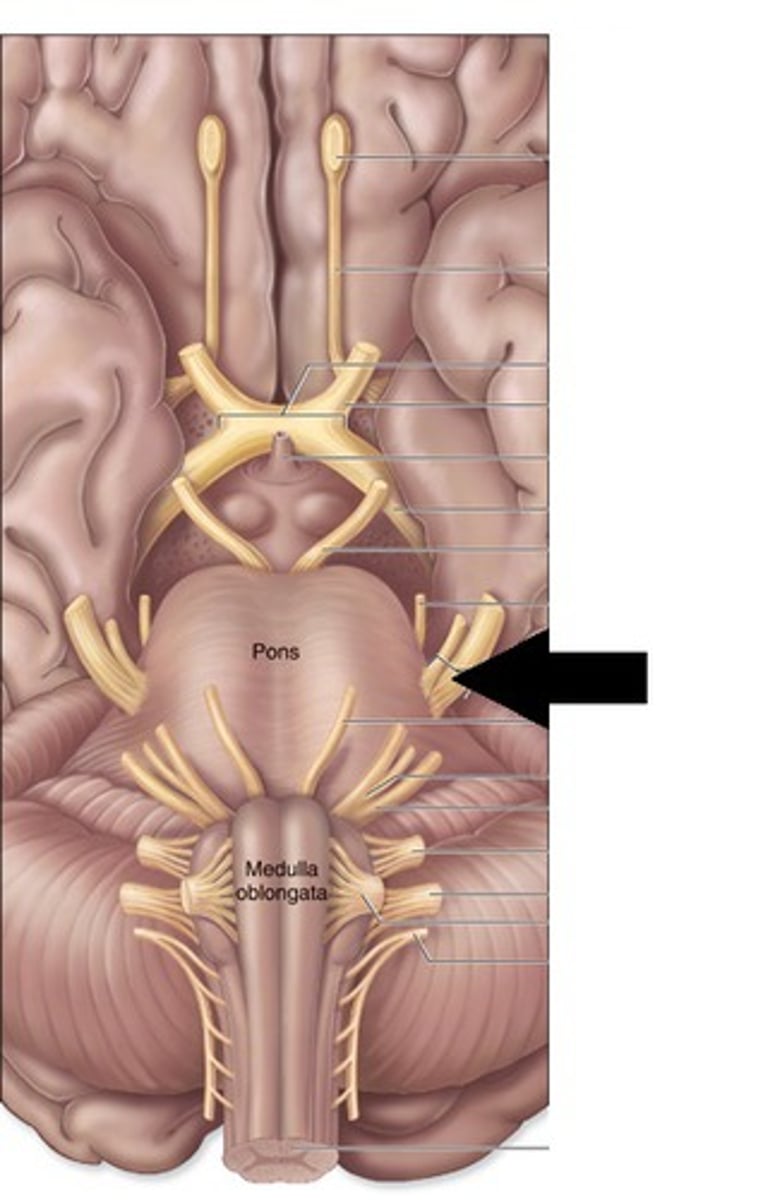

pons

center structure of the brain stem, located between the midbrain and the medulla oblongata

trigeminal nerves

regulates sensory input from head & face, governs chewing

abducens nerves

controls eyeball movement, particularly abduction (outward gaze)

facial nerves

regulates facial movements, saliva, tears

vestibulocochlear nerves

the vestibular and cochlear nuclei in the pons are involved in balancing and hearing